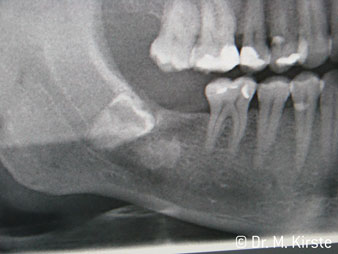

45° ъгъл на наконечника е специално избран поради неговата широка гама от предимства. Колеги, които работят хирургия, и за които този наконечник е главно създаден, скоро ще оценят възможността за ефективна работа в силно ограничени пространства. При екстрахиране на мъдреци, в частност (фиг. 2), няма нужда от голямо разширяване на меката тъкан в областта на бузата (фиг. 3). Дизайнът на главата на наконечника, в съчетание с лекото завъртане на главата по време на препарация, позволява бърза и безопасна работа в ретромоларната област.

Специалният дизайн на лагерите в главата на наконечника гарантира безшумен ход на борера; това прави впечатляващо атравматичен разрез при отделянето на зъба и корена (фиг. 4-9).